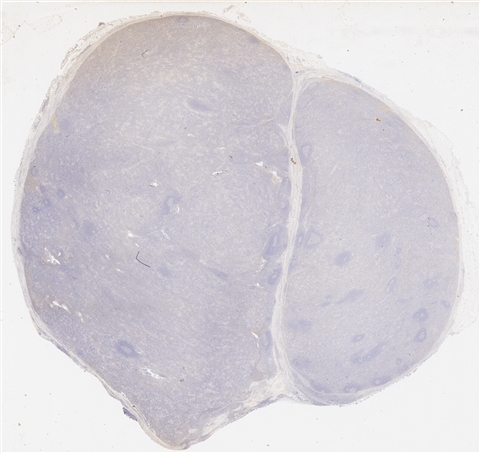

案例4 (6863)

性别:       年龄:48

患者详情: 患者4月余前体检行胸部CT检查示“右肺上叶混杂磨玻璃结节;纵隔多发肿大淋巴结可能”。3月前来我院门诊就诊,行胸部CT示“中纵隔右侧肿块,请结合穿刺;右锁骨区、纵隔及右肺门多发肿大淋巴结”。行纵隔肿块EBUS,显微镜下“见纤维素样渗出物及少量淋巴细胞、纤维样细胞及支气管上皮细胞,未见恶性依据”。行PET-CT检查示“右纵隔右侧肿块,FDG代谢增高;纵隔、双侧锁骨上小淋巴结,FDG代谢增高”。遂行纵隔肿块切除术。

大体所见: 送检“中纵隔肿瘤”一枚,大小5.5*4.5*4.0cm,包膜完整,切面灰黄质韧,中央见灰白星状瘢痕。

医院: 复旦大学附属肿瘤医院